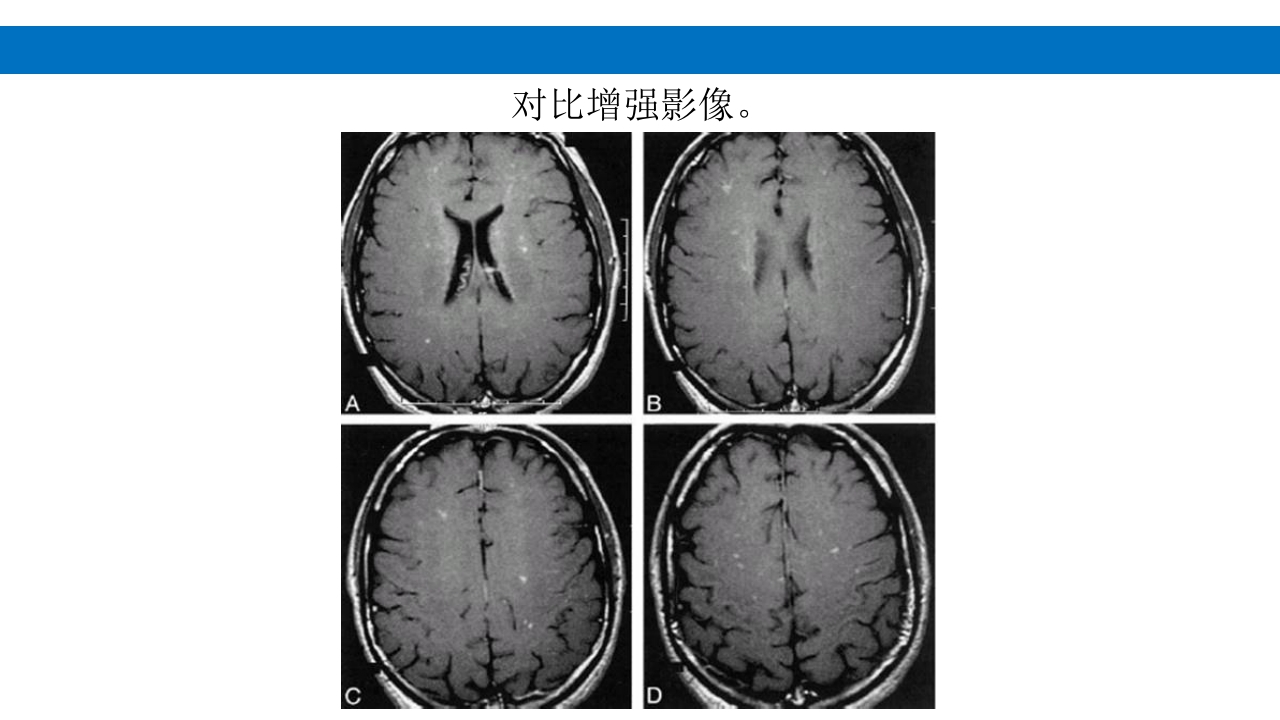

颅脑损伤的并发症及后遗症 讲解人:xxx 20XX年x月x日 1.颅骨骨髓炎 病因:为头皮软组织、中耳、乳突和副鼻窦等处炎性感染而经导 血管侵入颅骨内或颅脑开放伤感染所引起,亦可由菌血症后发生 的细菌栓子由血运转移至颅骨内。 影像学表现: 头部CT: 1.表现为不规则的蜂窝状骨质破坏区,主要位于板障,亦可累 及内外板。 2.破坏区内可见高密度的米粒状细小的高密度死骨。 3.周边可见骨质硬化增生,颅板外无骨膜反应。 4.局部的头皮可见软组织肿胀。 头部MRI: 由于受累部位细胞成分和水量增多,T1WI为低信号, T2WI为高信号,急性期边界不清,慢性期病灶局限, 边界清晰。MRI显示骨质破坏没有CT效果好。 治疗: 除应用抗菌药物控制感染外,当感染局限或已有死骨形成后, 应行手术切除感染...